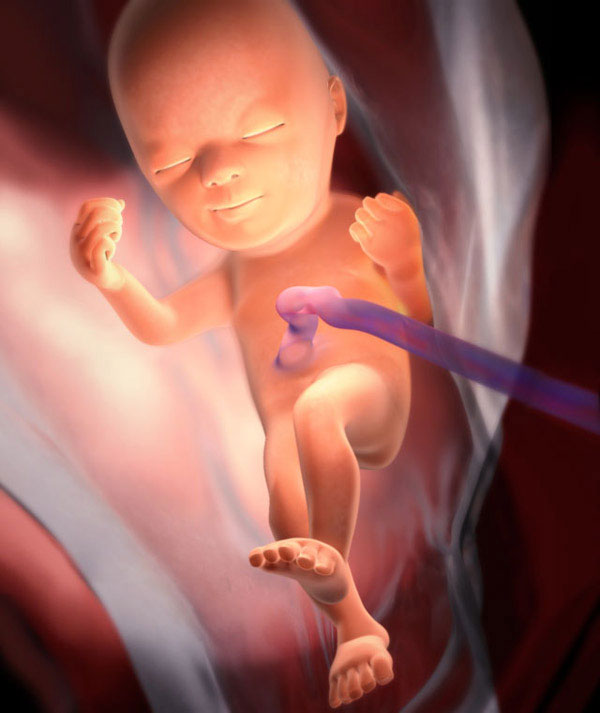

L'événement le plus important de cette semaine est que le fœtus achève le développement des bronches. Un surfactant se forme dans les alvéoles (vésicules pulmonaires). Il s'agit d'un surfactant spécial qui facilite les ballonnements des poumons pendant la respiration et ne leur permet pas de coller ensemble lorsqu'ils expirent. C'est un surfactant qui assure une préparation respiratoire. Les médecins appellent donc la capacité de respirer si le bébé naît prématurément.

Les proportions du corps fœtal sont près de 100% proches des paramètres du nouveau-né. La seule différence est que le bébé a l'air mince, avec des bras et des jambes très fins et une peau ridée. En effet, la couche de graisse sous-cutanée n'est pas complètement formée.

Voici à quoi ressemble le fœtus à 24 semaines:

Toujours en cours:

- minéralisation osseuse;

- la formation de gyrus cérébral;

- mouvements réflexes (déglutition, respiration, mouvements);

- un cœur développé compte environ 140-160 battements par minute.

Environ 16-20 heures, le fœtus dort, le reste du temps éveillé. Dans de rares cas, les mères ne ressentent toujours pas les mouvements de leur bébé. La 24e semaine, cela doit arriver.